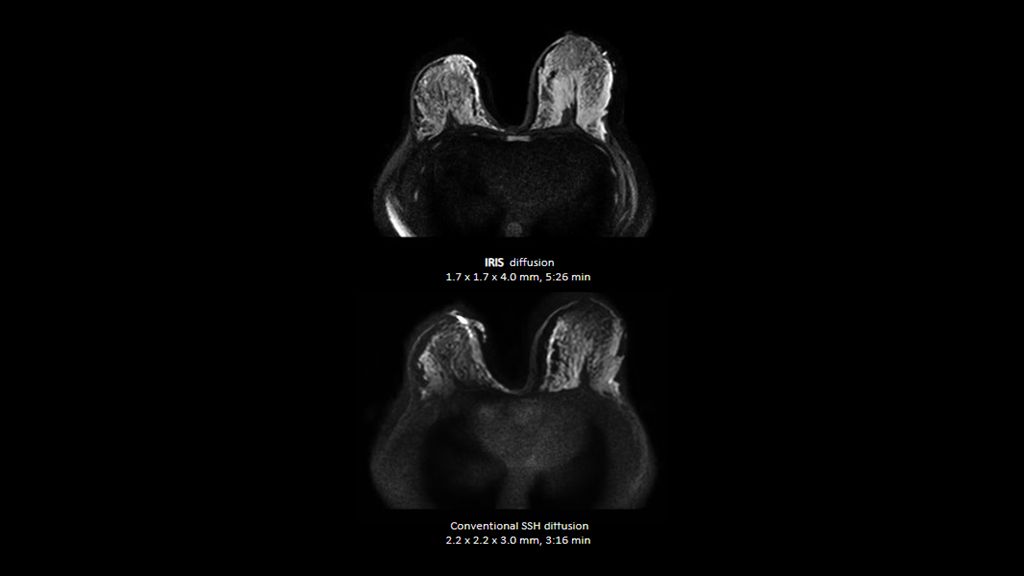

Philips - SmartSpeed Precise- Breast NMRF445C - Philips